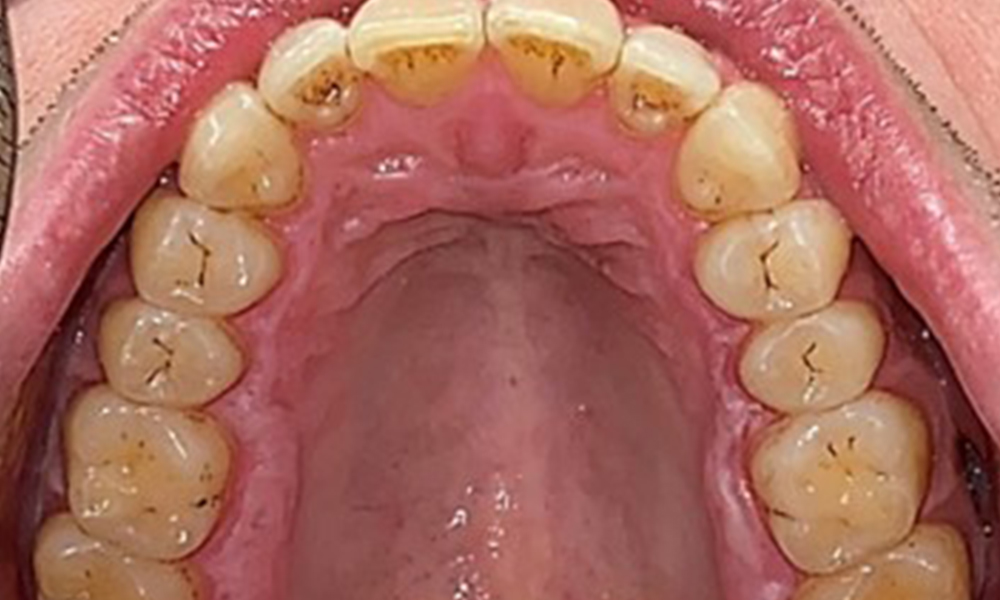

Okklusalansicht Oberkiefer

Abb. 3: Okklusalansicht Oberkiefer, © Dr. R. Krapf

Extraoral sind keine pathologischen Befunde festzustellen, intraoral zeigen sich bei der Frontalansicht im Bereich der keratinisierten Gingiva und am Übergang zur beweglichen Schleimhaut bräunlicheVerfärbungen (Abb. 2), welche auf den Nikotingenuss zurückzuführen sind. Am Gaumenbereich zeigen sich insbesondere im Bereich Oberkiefermolaren palatinal weißliche Schleimhautveränderungen, die ein Hinweis auf einen erhöhten Verhornungsgrad sind und ebenso auf den Nikotingenuss zurückzuführen sind. Die Zunge ist mit einem weiß-bräunlichen abwischbaren Belag versehen.

Dental zeigt sich ein vollbezahntes Gebiss mit 28 Zähnen. Auffällig sind Erosionen und Attritionen

(Abb. 4, Abb. 5). Der Patient trägt seit vielen Jahren nachts eine Schiene mit adjustiertem Aufbiss aufgrund Bruxismus. Die Erosionen sind auf den langjährigen Konsum isotonischer Getränke zurückzuführen. Parodontaler Knochenverlust und aktive kariöse Läsionen sind nicht vorhanden.